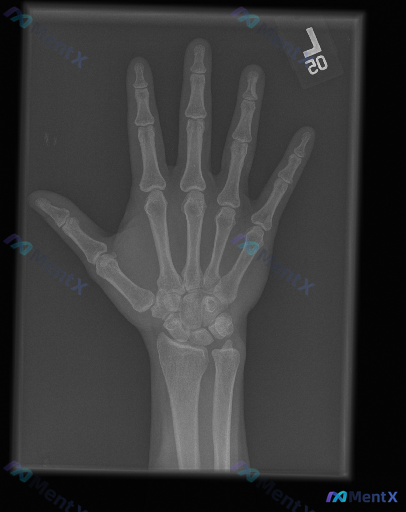

整理到一个影像相关的病例情况,想和大家讨论下判断思路: - 影像资料:左手正位X光片 - 读片所见:各指骨、掌骨、腕骨皮质连续,未见明确骨折线、脱位或半脱位;骨小梁清晰,密度均匀,无明显骨质破坏、骨膜反应或异常钙化;各关节间隙对称、宽度正常,关节面光滑,无明显骨赘或侵蚀;周围软组织轮廓自然,未见明显...

整理到一组影像与临床结合的资料,想和大家讨论下这种情况的思路: 基本情况: - 影像学检查:双侧手部正位X光 - 影像所见:骨骼结构完整,骨皮质连续,未见明确骨折线、脱位;各关节间隙尚可,未见明显狭窄或破坏;骨密度、骨端形态大致正常;软组织影未见明确肿胀、钙化或占位。 - 影像初步总结:双侧手部正位...